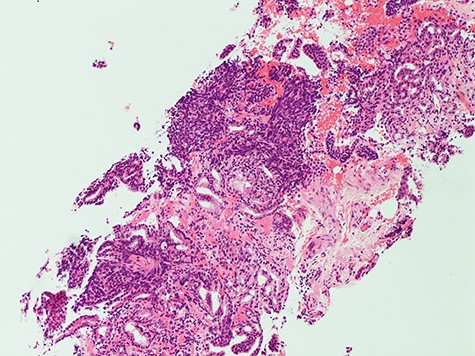

Histology from trans-rectal ultrasound (TRUS) biopsy of the prostate showed a conventional microacinar type prostatic adenocarcinoma of Gleason score 4 + 4 = 8 with an intermingled component of SCC, composed of cohesive sheets of small cells with scant cytoplasm, hyperchromatic nuclei and nuclear molding with increased mitotic activity (Fig. 2). The cytomorphology was similar to the neck FNA. The small cell component showed positive staining for neuroendocrine markers Synaptophysin and CD56. The Ki-67 index was 70%. PSA showed scattered positivity. Overall, the features were consistent with a mixed microacinar adenocarcinoma and SCC. Following the diagnosis from TRUS biopsy, PSA immunostain was carried out on the FNA material, which showed scattered positivity.